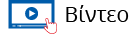

Το TomoTherapy είναι το μοναδικό ακτινοθεραπευτικó μηχάνημα με ενσωματωμένο αξονικό τομογράφο που θεραπεύει όλο το φάσμα των ασθενών που χρήζουν ακτινοθεραπείας.

Δίνει τρισδιάστατη κατανομή της δόσης ακτινοβολίας με υψηλή ακρίβεια σε μια περιστροφή 360° του γραμμικού επιταχυντή, σε εξαιρετικά σύντομο χρόνο (5-10'), παρέχοντας εξαιρετική προστασία των υγιών ιστών, μέσω μια υπεραπλουστευμένης για τον ασθενή θεραπευτικής διαδικασίας.

Μοιάζει με ευρύχωρο αξονικό τομογράφο, ενώ η αξιοπιστία του και η ευκολία στον χειρισμό, το καθιστά ικανό να απλοποιεί ακόμη και τα πιο σύνθετα περιστατικά μετατρέποντας τα σε απλά.